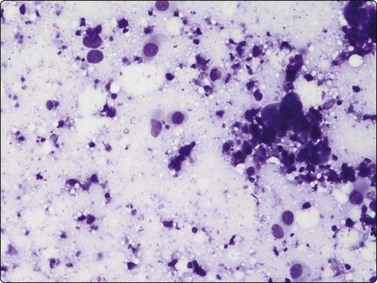

Breast tissue in pregnancy and lactation (Fig. 7.8)

image image image

Fig. 7.8 Lactating breast

Dispersed acinar cells with abundant pale and fragile cytoplasm, rounded nuclei and prominent central nucleoli; background of lipid secretions (A, MGG, HP; B, H & E, HP oil); (C) Corresponding tissue section (H&E, IP).

Criteria for diagnosis

Cellular smears,

Poorly cohesive, mainly dispersed epithelial cells of acinar type,

Cells have abundant fragile cytoplasm with secretory vacuoles and frayed borders,

Rounded vesicular nuclei and central nucleoli,

Dirty background due to lipid secretion and stripped nuclei with prominent nucleoli,

Single bipolar nuclei difficult to find.

FNB is very useful in reducing surgical intervention to a minimum during pregnancy and lactation. The pattern seen in FNB smears of ‘lumps’ in a pregnant or lactating breast can be problematic to inexperienced eyes and cause concern for malignancy.93,94 Smears are usually cellular. The cells are enlarged and arranged in loose groups or singly. The cells have an abundant fragile cytoplasm, vacuolated and finely granular. Nuclei are round, central, larger than the usual ductular cells, and have distinct small nucleoli (Fig. 7.8B). Some epithelial nuclei are stripped of cytoplasm. Single naked bipolar/oval nuclei are difficult to find. The background of abundant milky secretion with numerous lipid droplets seen as vacuoles is characteristic of actively secreting breast tissue and is the main clue to the diagnosis (Fig. 7.8A).